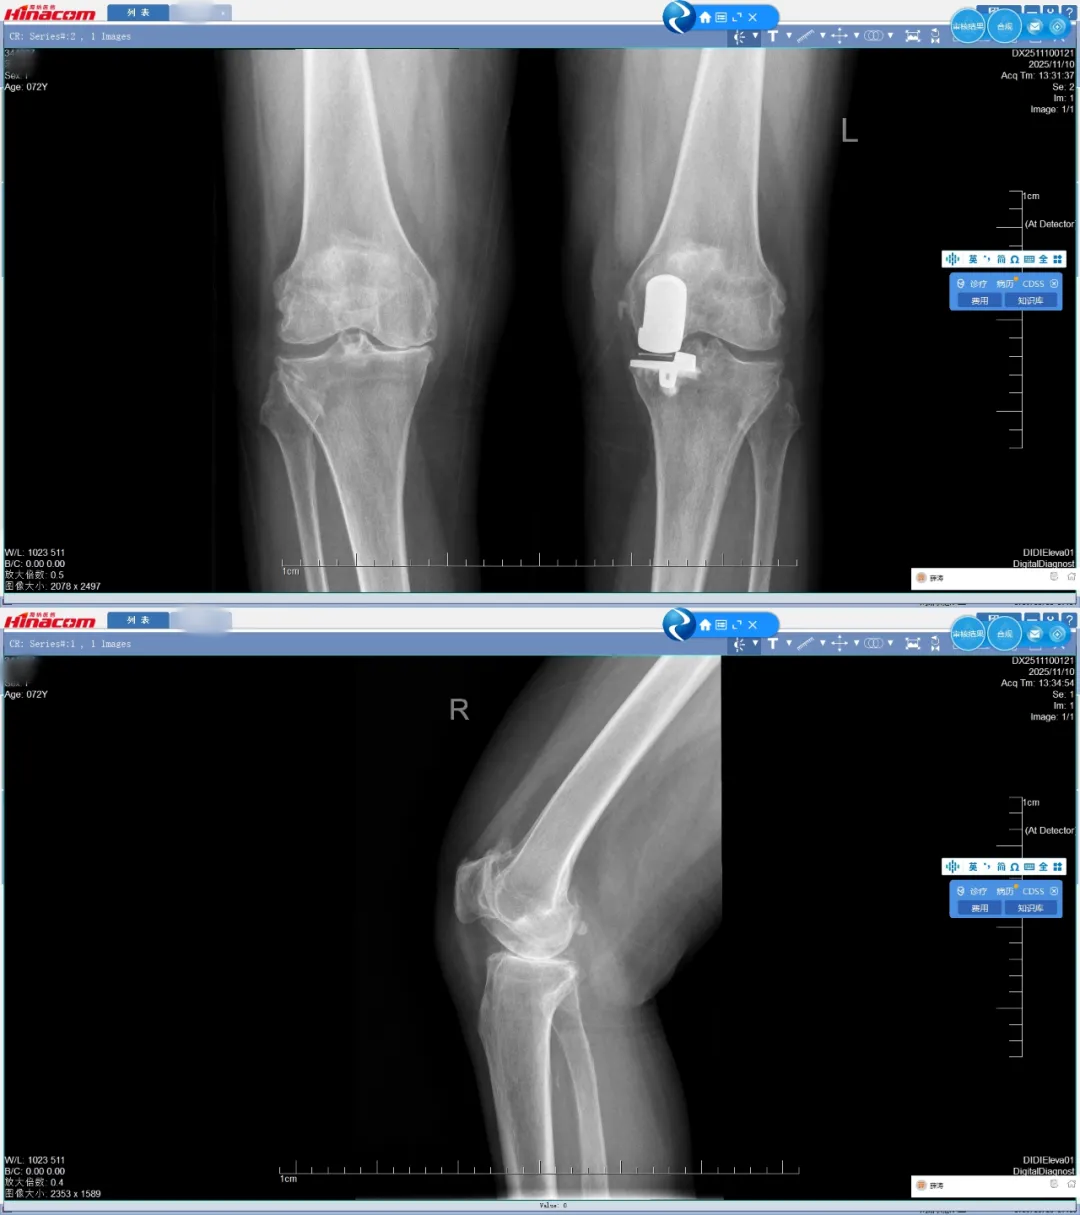

just机器人术前规划

术前正、侧位

这场手术的核心“主角”之一,正是 JUST 骨科机器人。术前,医疗团队将宋女士的影像学资料精准输入系统,如同为机器人配备了“火眼金睛”,在数字空间里完成了毫米级的手术规划,明确假体型号、截骨角度和位置,为手术搭建起精准的“导航地图”。手术当天,机器人的机械臂像一位精准默契的“助手”,与医生的操作无缝配合,将摆锯的运动范围严格限定在预设安全区域内,避开重要神经和血管,实现了股骨、胫骨的精准截骨和假体安放,整个过程如同在毫厘之间“穿针引线”。